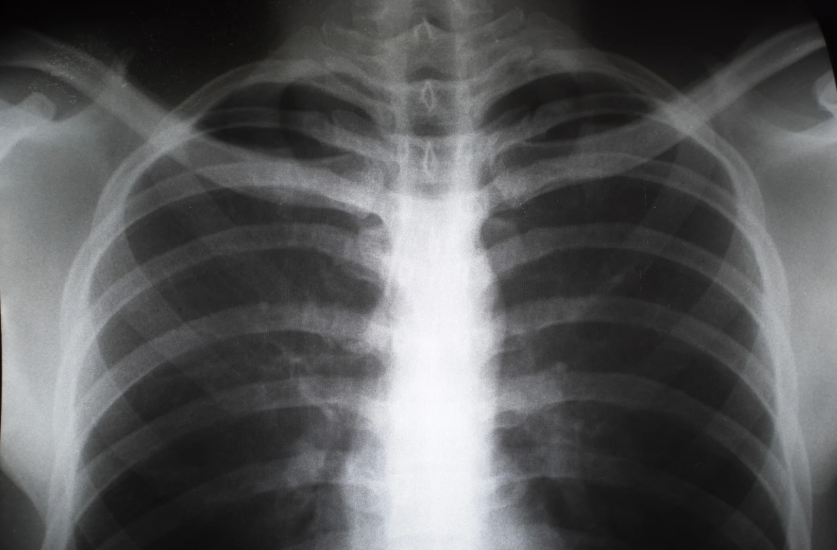

2) 흉부 X-ray

- 흉부 X-ray는 폐렴을 진단하는 가장 중요한 도구입니다. 폐렴이 있을 경우 폐의 염증이나 침윤이 나타나게 됩니다.